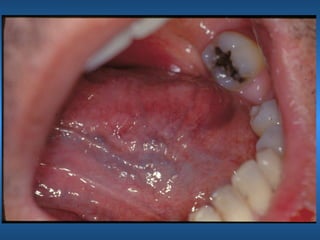

Leucoedema

• Etiologia

• Características Clínicas

• Raça

• Manobra Clínica

• Aspectos Histológicos